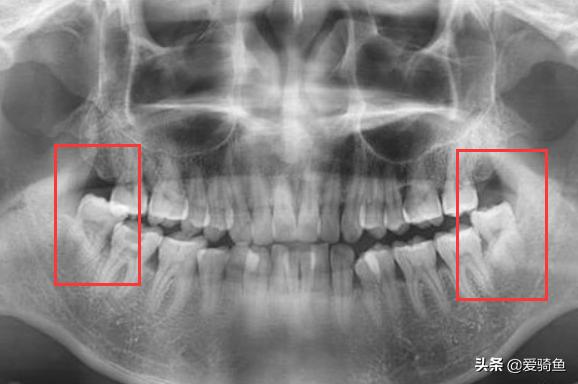

X片

下颚俩垂直阻生智齿